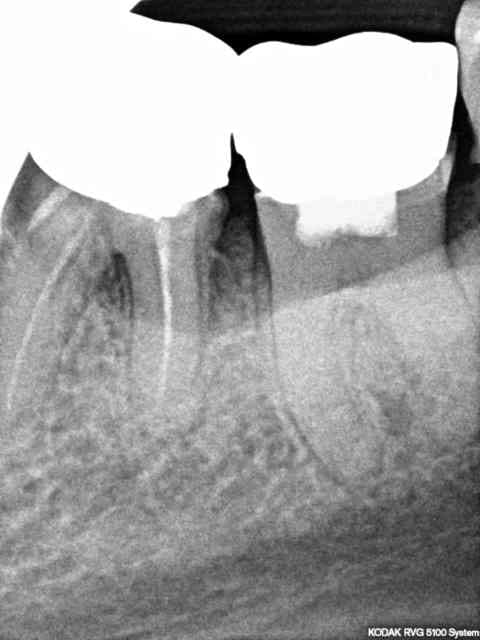

je viens de recevoir une patiente qui va se faire poser une prothèse de hanche dans 2 mois.

Dans un temps aussi court est-ce qu'il vous parait

possible de remettre en état sans pratiquer des extractions multiples, les endos sur 15 et 47 sont pratiquement inexistantes , bridge sur dents vivantes , tout est assymptomatique, 48?

désolée ... voici les radios

oups il manque celle là..